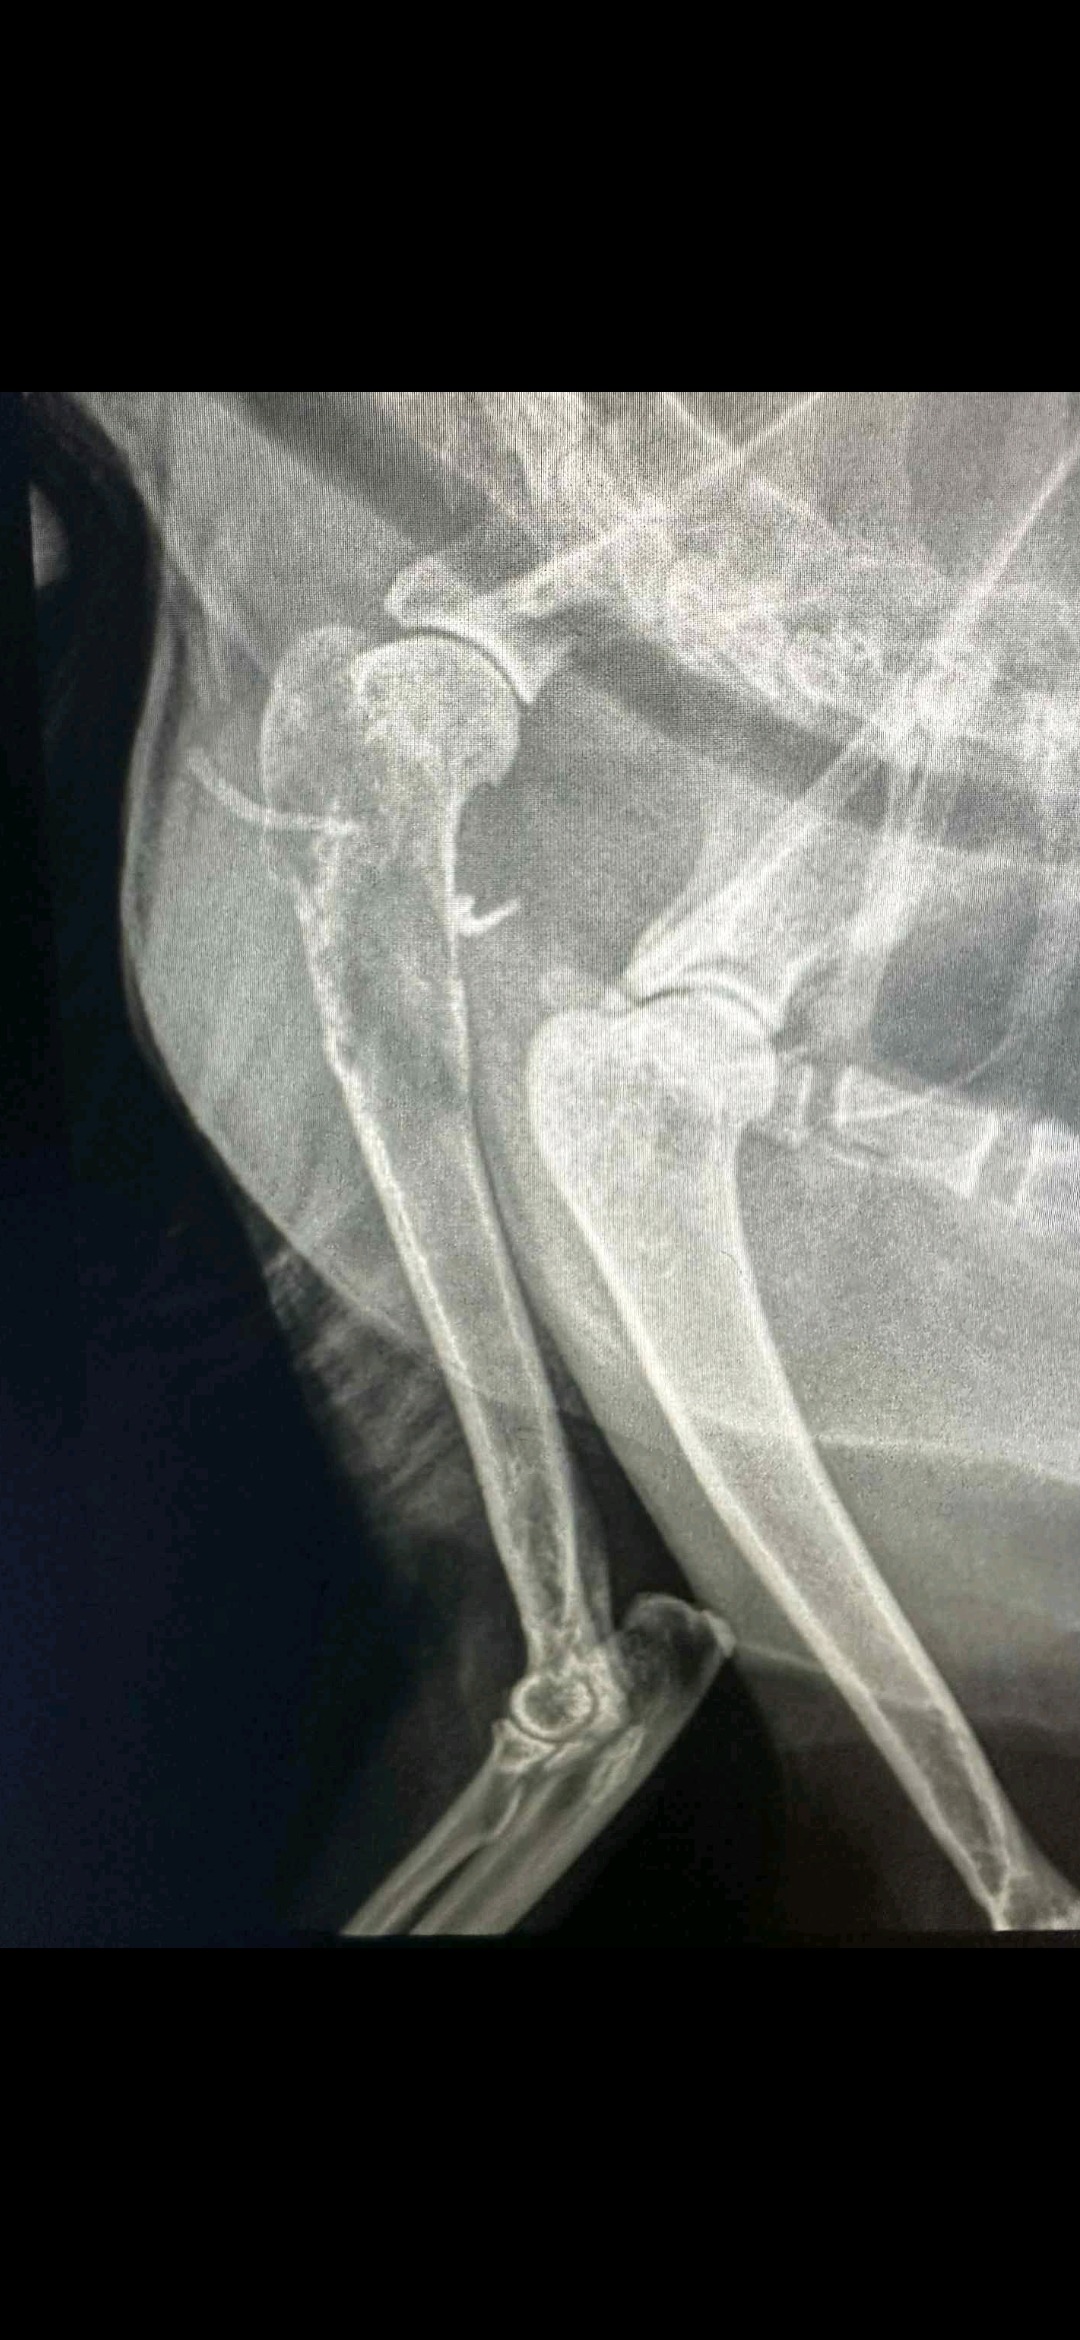

Poor Gilbert started limping a few weeks ago. I thought it might have just been a sprain or something minor. I finally took him to see the vet this morning, and it ended up being much more devastating. This poor guy has bone cancer eating away at his leg. I feel so bad for him. He's about 14 years old and is still eating and drinking, purring, and getting around. My 3 daughters love this guy, but unfortunately, the cost of amputation to keep him around a few more years is just not in the cards. I didn't put him down today as he is still healthy otherwise for now, and his bloodwork was all perfect. He's clearly in pain, and it's sad to see. I'm going to treat him with some medications to keep him comfortable and told the girls to give him lots of love. I don't expect him to last too long with a bone looking that bad untreated. Though our plan of care is keeping him comfortable, my girls have asked why I'm not doing more. He would likely fully recover and live a normal life on 3 legs, but the cost to amputate is quite a bit. I told my daughters I would do all that I can. So, I figured I'd start a GoFundMe to see if anyone could help.